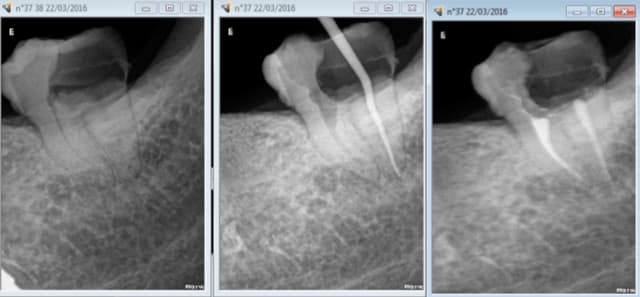

Mais ca marche aussi pour les SC 33. -)))

J'aime bien le sc 33 mais quand je ne peux pas faire d'inlay core. -))))

je risque un indu car je sors de l'indication du SC33 ? -))))

1H TTC. -)))

Capture d e cran 2016 03 22 17.11 - Eugenol

Capture d e cran 2016 03 22 17.13 - Eugenol